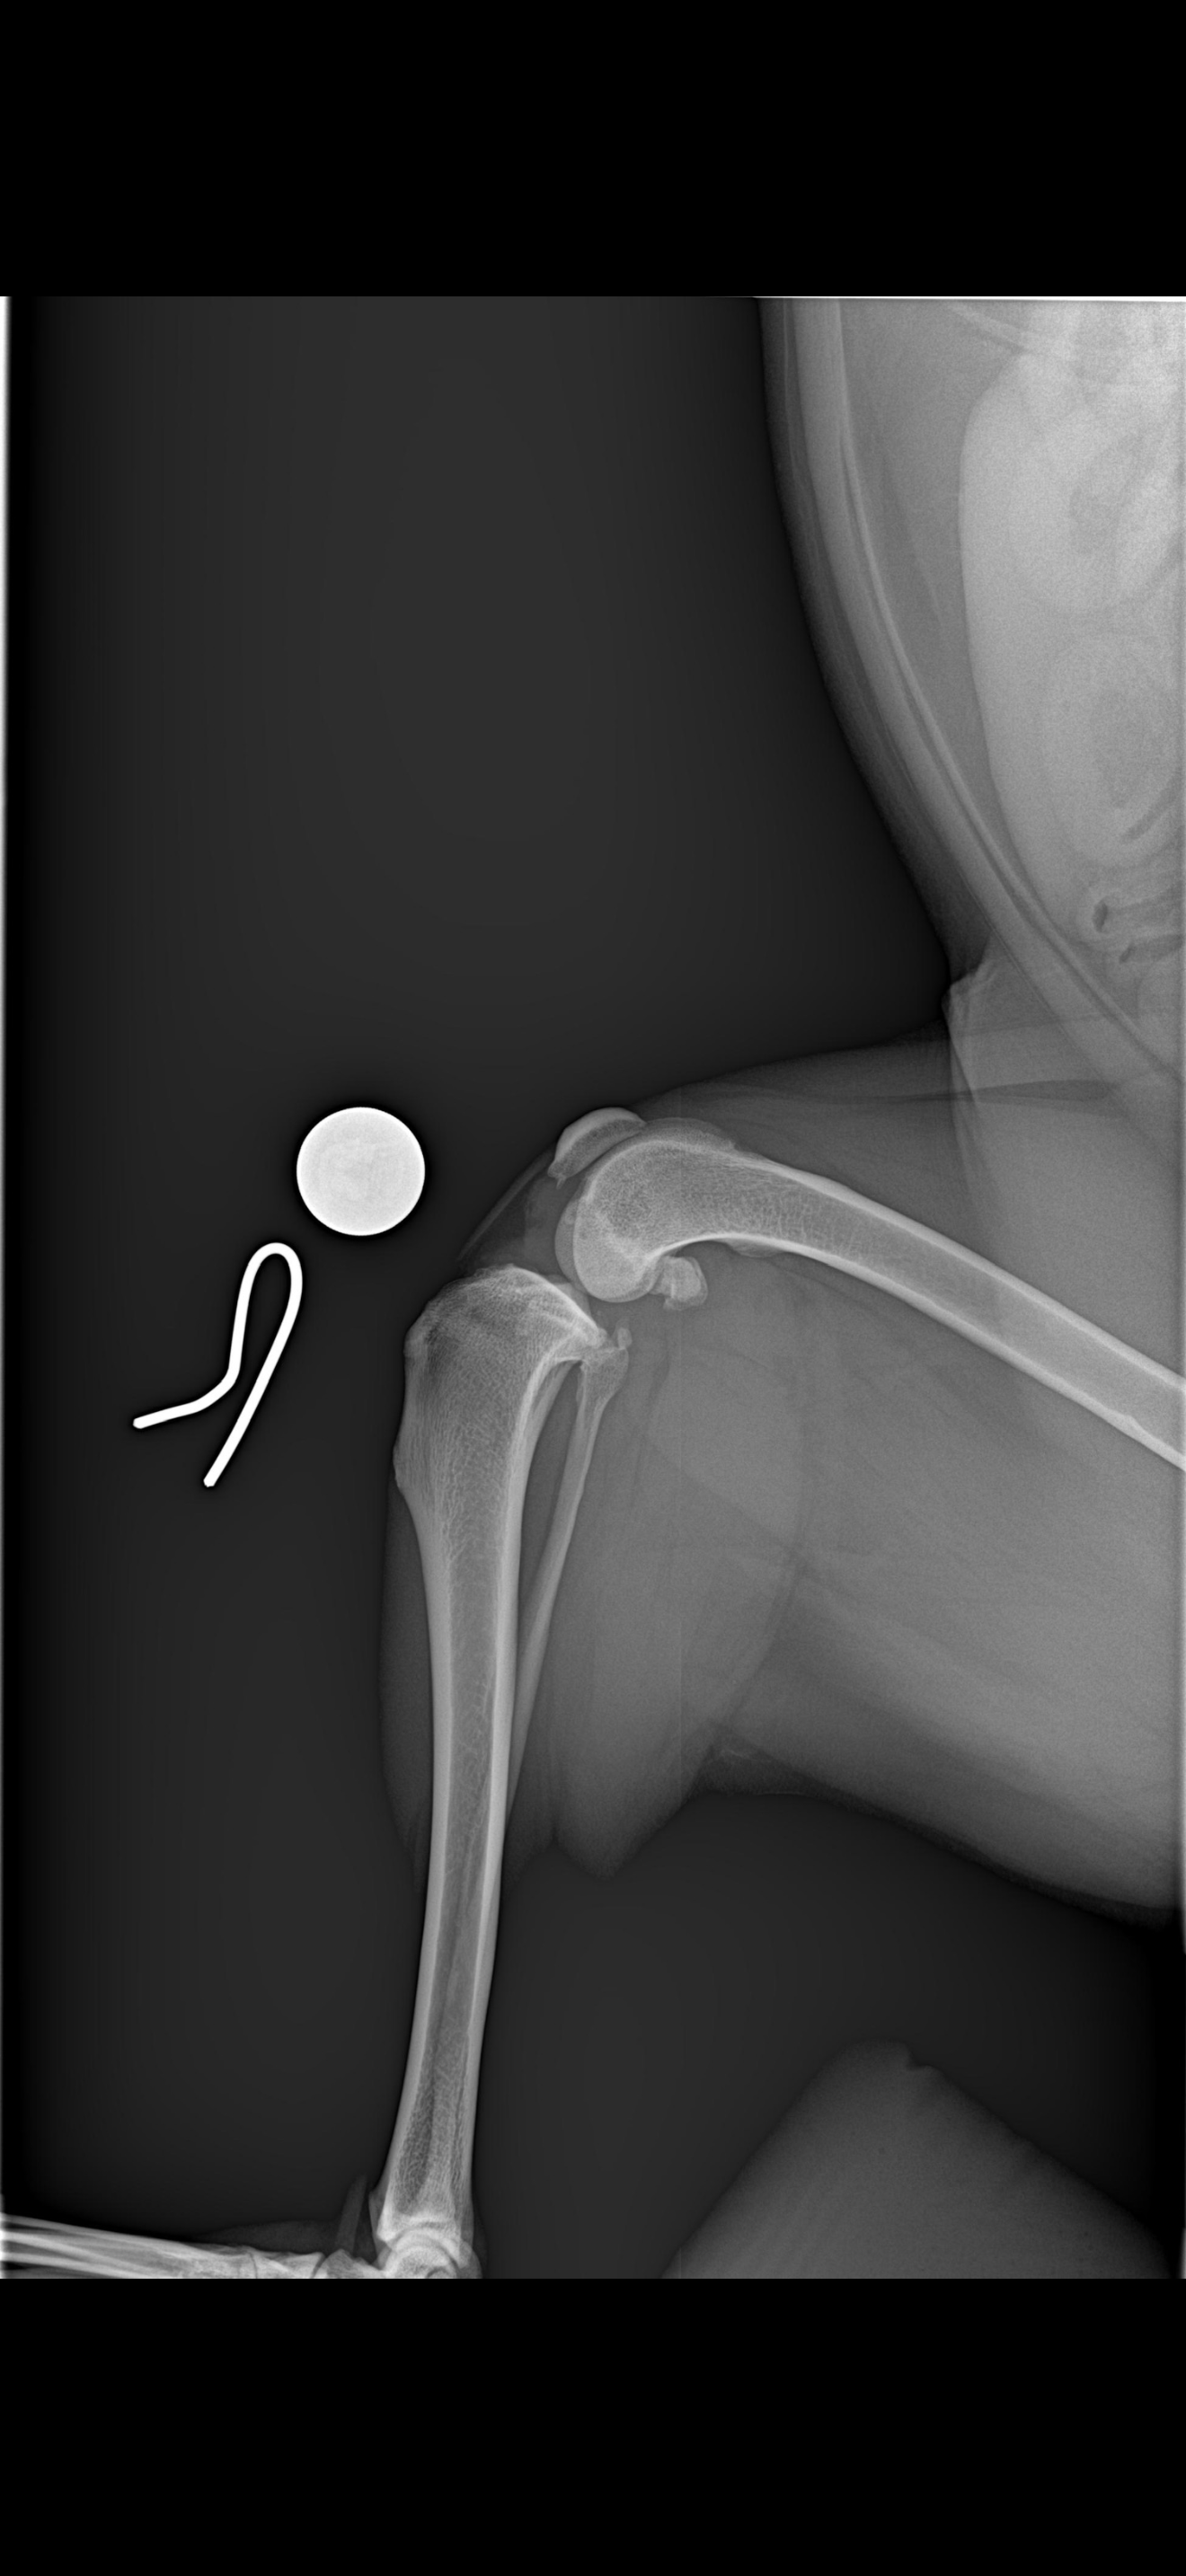

A few years ago, Lola was diagnosed with a partial cranial cruciate ligament tear. We managed her condition with medications and therapy for as long as possible. Unfortunately, a few months ago, her injury progressed to a complete rupture. Since then, even a small wrong step can cause severe pain and has led to multiple emergency vet visits.

Lola now needs TPLO surgery to repair her ligament and give her a chance to live a pain-free life again. The total estimated cost for her care ranges from $8,000 to $13,000.